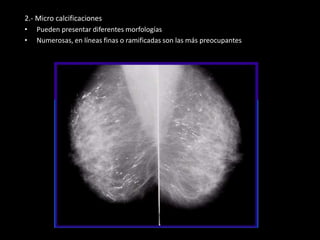

2.- Micro calcificaciones

• Pueden presentar diferentes morfologías

• Numerosas, en líneas finas o ramificadas son las más preocupantes